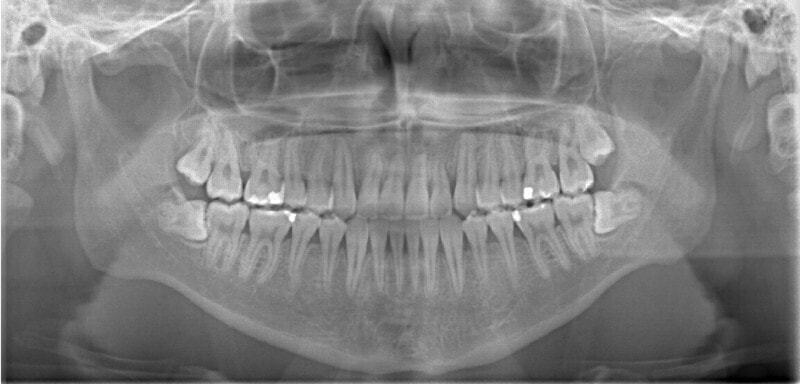

治療後(2年1ヶ月後)

治療中のレントゲンです。

7番、8番の状態や歯根のパラレリング(平行性)をチェックしています。

左上2番の歯根の状態もなんとかもちそうです。

下顎の右側への偏位は解消されました。

大臼歯は整直されております。

歯根のパラレリングは良好です。

左上2番の歯根も問題なさそうです。

下顎8番は保定期間に入り、しばらくして咬合が安定してから抜歯する予定です。

特に左側の咬合時の顎関節の位置に改善が認められます。